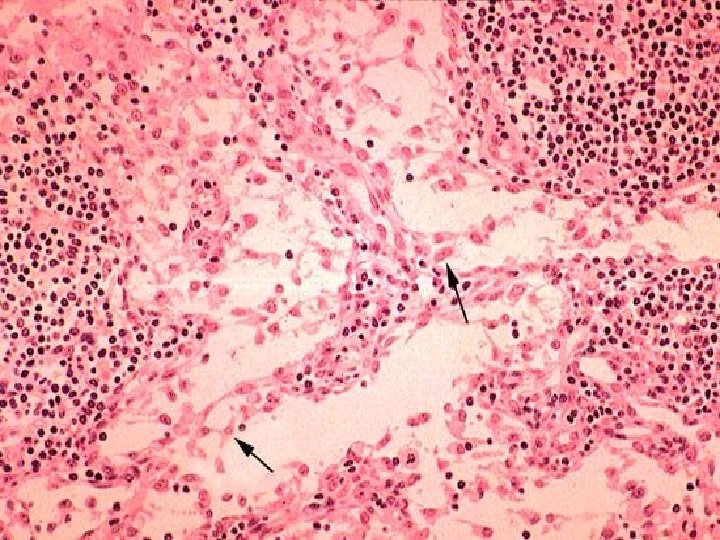

LOOSE Connective Tissue: 3. Reticular CT – Consists of fine interlacing reticular fibers and reticular cells – Found in liver, spleen and lymph nodes – Function = forms the framework (stroma) of organs and binds together smooth muscle tissue cells